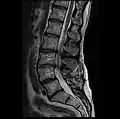

MRI lumbar spine with degeneration, post-hemilaminectomy L4-5 (sagittal T2 FRFSE)

MRI lumbar spine with degeneration, post-hemilaminectomy L4-5 (sagittal T1 FSE)

MRI lumbar spine with degeneration, post-hemilaminectomy L4-5 (sagittal FAST STIR)- MRI lumbar spine post-hemilaminectomy (sagittal T2 FRFSE)